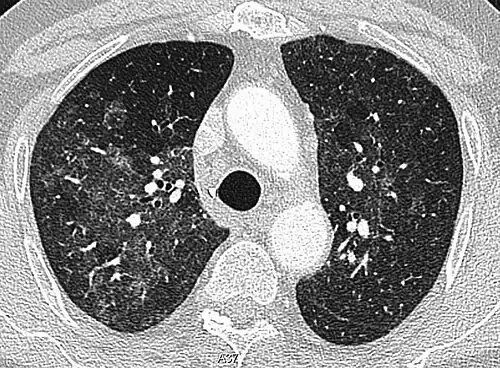

CT image showing patchy areas of ground-glass opacities representing pulmonary edema.

The diffuse pattern typically refers to GGOs in multiple lobes of one or both lungs. Broadly, a diffuse pattern of GGO can be caused by displacement of air with fluid, inflammatory debris, or fibrosis. Cardiogenic pulmonary edema and ARDS are common causes of a fluid-filled lung. Diffuse alveolar hemorrhage is a rarer cause of diffuse GGO seen in some types of vasculitis, autoimmune conditions, and bleeding disorders.[6]